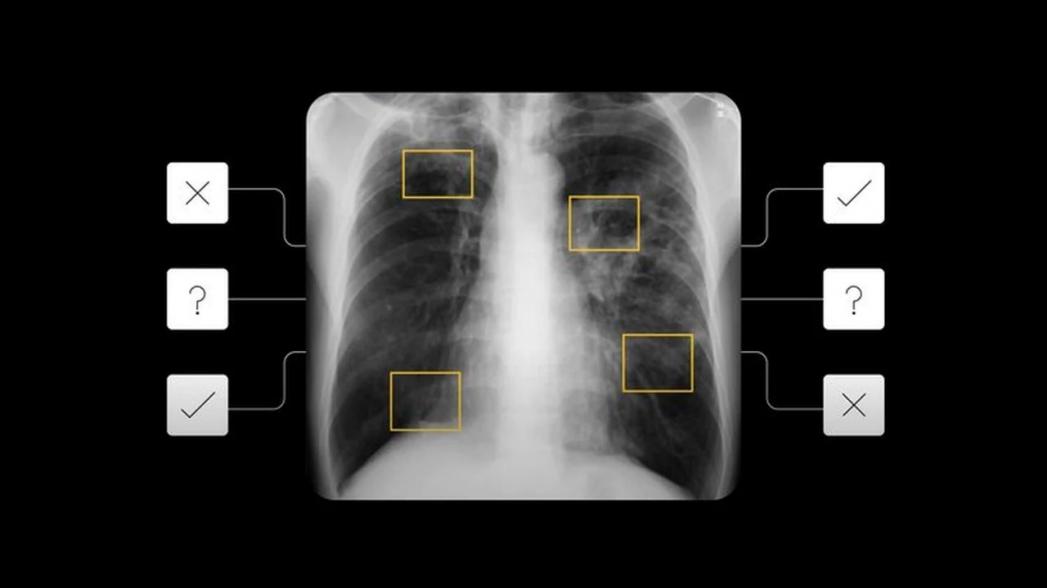

Чтобы помочь выявить болезнь на ранней стадии, исследователи Google разработали инструмент на основе искусственного интеллекта, который, опираясь на существующие наработки компании в области анализа медицинской визуализации, позволяет выявлять потенциальных пациентов с туберкулезом для последующего тестирования.

Система Google смогла точно выявить активные случаи легочного туберкулеза с показателями ложноотрицательных и ложноположительных результатов, которые были аналогичны показателям 14 рентгенологов. Такая точность сохранялась даже при обследовании ВИЧ-положительных пациентов - группы населения, которая подвержена повышенному риску развития туберкулеза и которую сложно обследовать, поскольку рентгеновские снимки грудной клетки у них могут отличаться от типичных случаев этой болезни.

Чтобы убедиться в том, что модель работает для пациентов самых разных рас и этнических групп, Google использовал для обучения модели деидентифицированные данные из девяти стран и протестировал ее на пациентах из пяти стран. Эти результаты основываются на предыдущих исследованиях Google, которые показали, что искусственный интеллект может обнаружить такие распространенные проблемы, как коллапс легких, узелки или переломы на рентгеновских снимках грудной клетки.

Система искусственного интеллекта выдает число от 0 до 1, которое указывает на риск заболевания туберкулезом. Для того чтобы система была полезной в реальных условиях, необходимо соглашение о том, какой уровень риска указывает на то, что пациентам следует рекомендовать дополнительное тестирование. Калибровка этого порога может занять много времени и средств, поскольку администраторы могут прийти к этому числу только после запуска системы на сотнях пациентов, тестирования этих пациентов и анализа результатов.